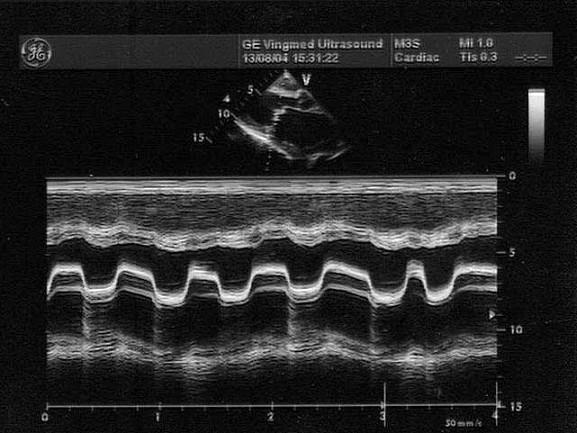

该病例最有可能诊断?(?)A.左房黏液瘤B.主动脉瓣关闭不全C.二尖瓣狭窄D.二尖瓣关闭不全E.二尖瓣脱垂

问题 该病例最有可能诊断?(?)

选项 A.左房黏液瘤 B.主动脉瓣关闭不全 C.二尖瓣狭窄 D.二尖瓣关闭不全 E.二尖瓣脱垂

答案 C